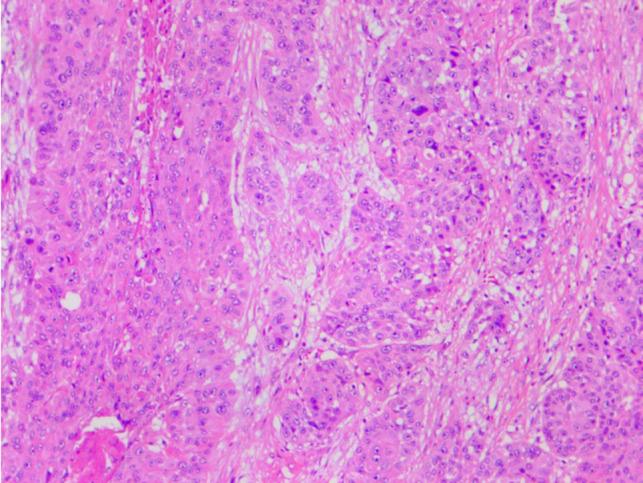

食管癌合并2型克里格勒-纳贾尔综合征患者的围手术期管理:一例报告

Perioperative Management of Patient with Esophageal Carcinoma and Crigler-Najjar Syndrome Type 2: A Case Report.

A 65-year-old male presented to our hospital with a choking sensation after eating. A physical examination showed yellowing of the sclera and skin. The patient manifested persistent jaundice since birth and had visited many hospitals, but the cause remained undiagnosed. We performed genetic testing, which confirmed CNS-II. Gastroscopy indicated esophageal carcinoma. A multidisciplinary team discussion was carried out to determine the appropriate treatment and perioperative management for this patient. The results show that surgical resection was the most appropriate approach. Finally, the patient underwent thoracoscopic surgery for esophageal carcinoma without complications.

一名65岁男性因进食后有哽咽感前来我院就诊。体格检查发现巩膜和皮肤发黄。该患者自出生以来一直表现为持续性黄疸,曾就诊于多家医院,但病因仍未确诊。我们进行了基因检测,确诊为CNS-II。胃镜检查显示为食管癌。组织了多学科团队讨论,以确定该患者的合适治疗方法和围手术期管理。结果表明手术切除是最合适的方法。最后,该患者接受了食管癌胸腔镜手术,未出现并发症。